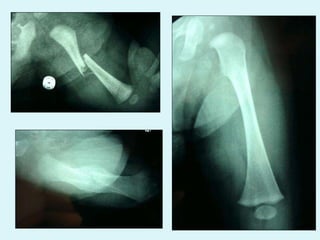

FRACTURE DU FEMUR

FRACTURE FEMUR